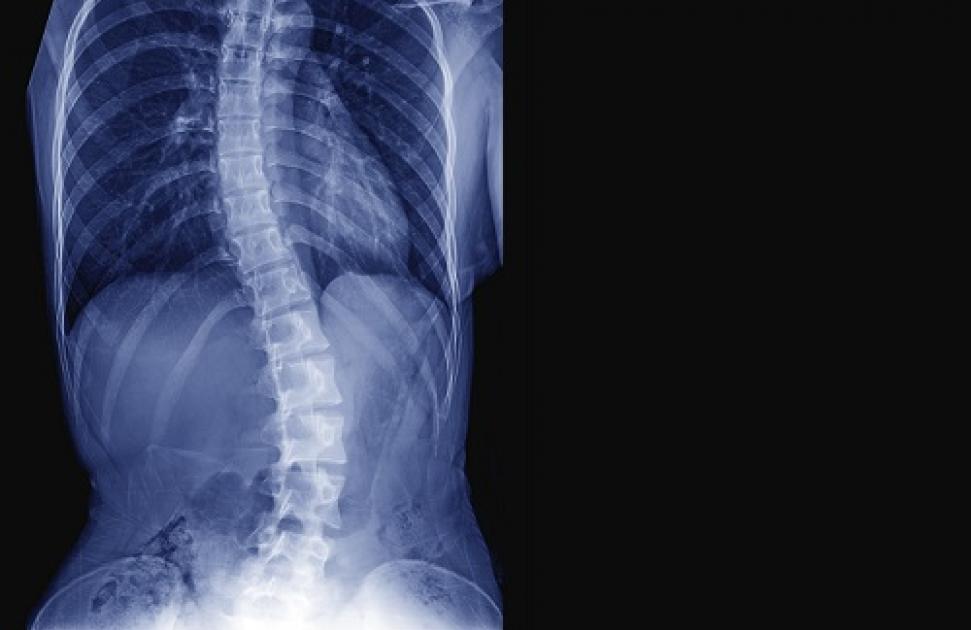

La scoliose idiopathique concernerait, en France, entre 0,5 et 2 % des 8-15 ans, principalement les filles, pour lesquelles l’incidence est 8 fois plus élevée que chez les garçons, estime la Cnam. De manière plus rare, des scolioses peuvent également apparaître à la suite d’une maladie neuromusculaire ou osseuse.

En cas de détection d’une scoliose, l’objectif est de limiter l’aggravation de la déformation du rachis, notamment chez les enfants et les adolescents : elle doit être la plus modérée possible à la fin de la croissance. Pour cela, les traitements de kinésithérapie et d’orthopédie, le port d’un corset et, pour les cas les plus sévères, un traitement chirurgical de la scoliose peuvent être envisagés.